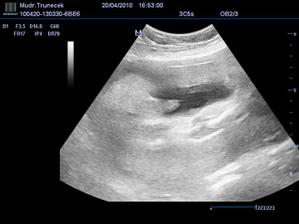

Dne 17.10.2009 mamka zjistila, že, ač neplánovaně, budu mít sourozence.TP je zatím 21. 6.2010.